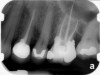

Fig 2. MTA placed in the apical third.

Figure 2

Fig 3. Postoperative radiograph.

Figure 3

Clinical procedure: If apical bone loss is present (Figure 1) a collagen/gelatin sponge (eg, Gelfoam®, Pfizer Inc., www.pfizer.com) can be placed apically so that the MTA can be delivered to the desired working length. (Any other surgical resorbable sponge would also work, such as OraPlug® [Salvin Dental Specialties, www.salvin.com], Surgifoam® [Midwest Dental, www.mwdental.com], or Surgispon® [Aegis Lifesciences, www.surgispon.com]). This is done by taking a small piece (2 mm x 2 mm) of the resorbable sponge and pushing it down to and through the root apex with an endodontic file. Once this is done, MTA is packed down the canal with a custom-fitted cone. The clinician can use a rubber stopper on the gutta-percha cone to know the exact length of MTA placed in the apical third (Figure 2). Once the apical third is sealed with 3 mm to 5 mm of MTA, the remaining coronal canal space can be back-filled using a warm gutta-percha technique (Figure 3).